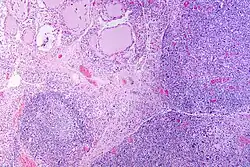

A micrograph of the thyroid of someone with Hashimoto's thyroiditis | |

Gross morphological changes within the thyroid are seen in the general enlargement, which is far more locally nodular and irregular than more diffuse patterns (such as that of hyperthyroidism). While the capsule is intact and the gland itself is still distinct from surrounding tissue, microscopic examination can provide a more revealing indication of the level of damage.[55] Hypothyroidism is caused by replacement of follicular cells with parenchymatous tissue.[52]

Pathology

Gross pathology of a thyroid with autoimmune thyroiditis may show a symmetrically enlarged thyroid.[5] It is often paler in color, in comparison to normal thyroid tissue, which is reddish-brown.[5]

Microscopic examination (histology) will show lymphocytes (including plasma B-cells) diffusely infiltrating the parenchyma.[55] The lymphocytes are predominately T-lymphocytes with a representation of both CD4+ and CD8+ cells.[5] The plasma cells are polyclonal, with present germinal centers resembling the structure of a lymph node[5] (also called secondary lymphoid follicles, not to be confused with the normally present colloid-filled follicles that constitute the thyroid).[55]

In late stages of the disease, the thyroid may be atrophic.[10] Colloid-filled follicles shrink, and the cuboidal cells that usually line the follicles become Hürthle cells.[5] Fibrous tissue may be found throughout the affected thyroid as well.[5] Severe thyroid atrophy presents often with denser fibrotic bands of collagen that remain within the confines of the thyroid capsule.[55]

Generally, pathological findings of the thyroid are related to the amount of remaining thyroid function — the more infiltration and fibrosis, the less likely a patient will have normal thyroid function.[5] A rare but serious complication is thyroid lymphoma, generally the B-cell type, non-Hodgkin lymphoma.[24]